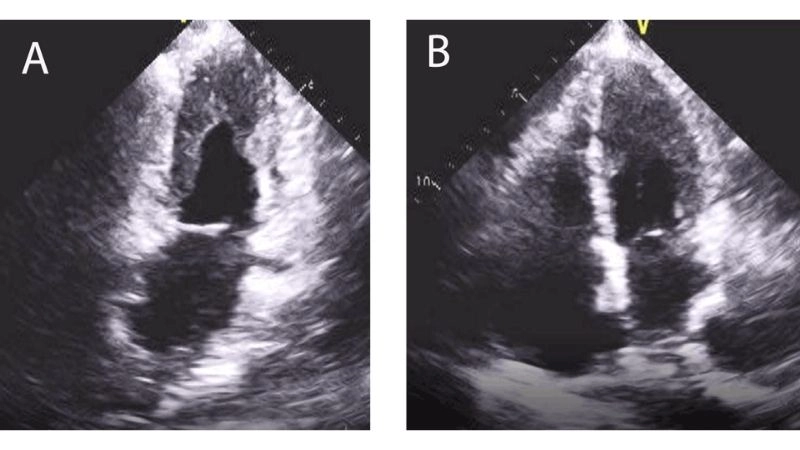

Images visual examples of Restrictive Cardiomyopathy (RCM)

Restrictive Cardiomyopathy (RCM) is a rare heart condition where stiffened heart walls limit blood filling. Images typically show thickened ventricles, atrial enlargement, and reduced relaxation on echocardiography scans.